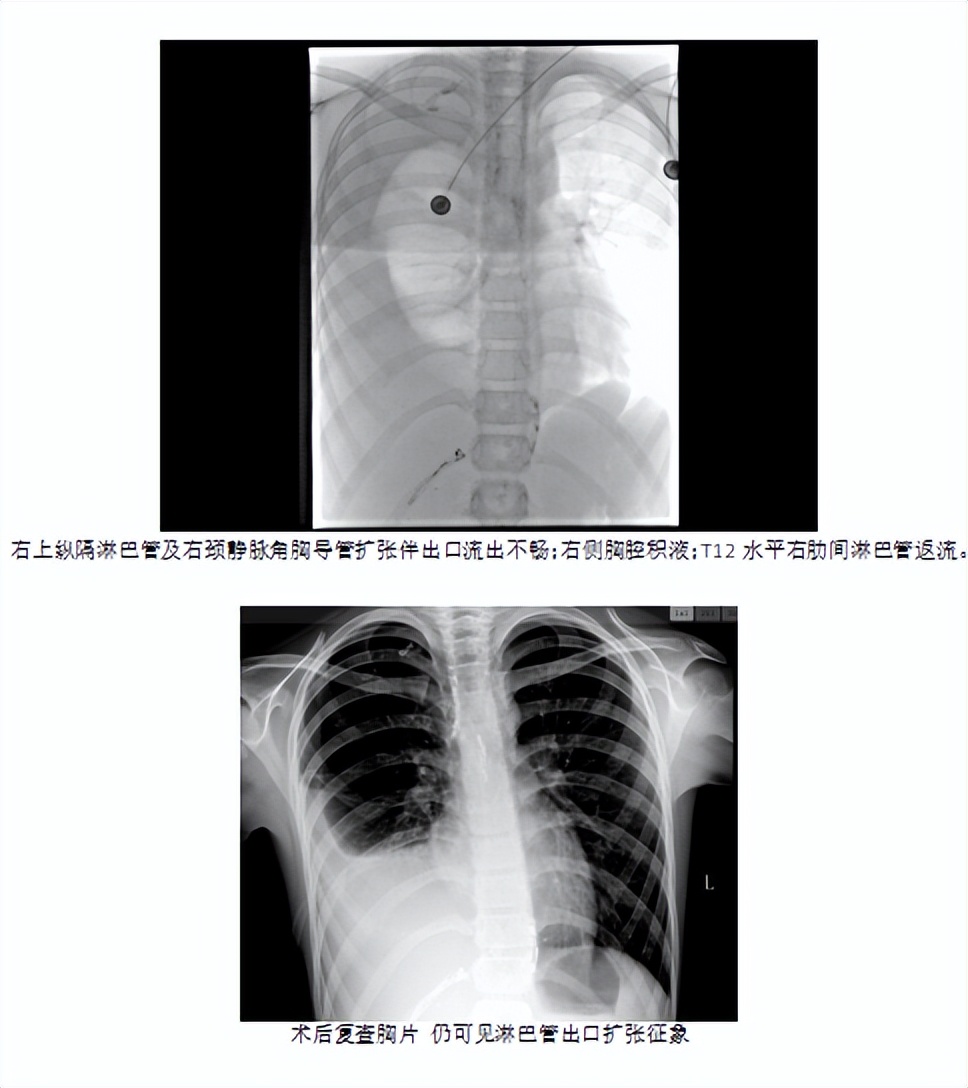

在安排的手术时间,家长如约住院,顺利完成术前准备,手术当天,患儿在全麻的过程中完成了手术,耗时3小时,应用穿刺针行淋巴结穿刺,注入碘油。显示:右上纵隔淋巴管及右颈静脉角胸导管右位引流,扩张伴出口流出不畅。右侧胸腔积液,T10-12水平右肋间淋巴管造影及返流。术后孩子也没有任何不适,身上也没有任何伤疤。共住院7天,患儿平稳出院。

术后患儿生命体征平稳,造影显示瘘口明确,拟行2次手术!期待患儿逐步恢复健康!